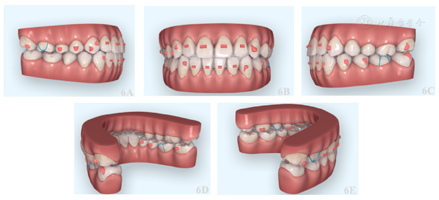

2.1双侧磨牙颌间牵引+左上及右下后牙舌侧椭圆附件辅助纠正左侧后牙反合、右侧后牙正锁合。

2.2左上颊、腭侧种植钉辅助下压低左上后牙,通过咬合跳跃,解决前牙及右侧后牙开合,达到双侧尖磨牙I类咬合关系(图6)。